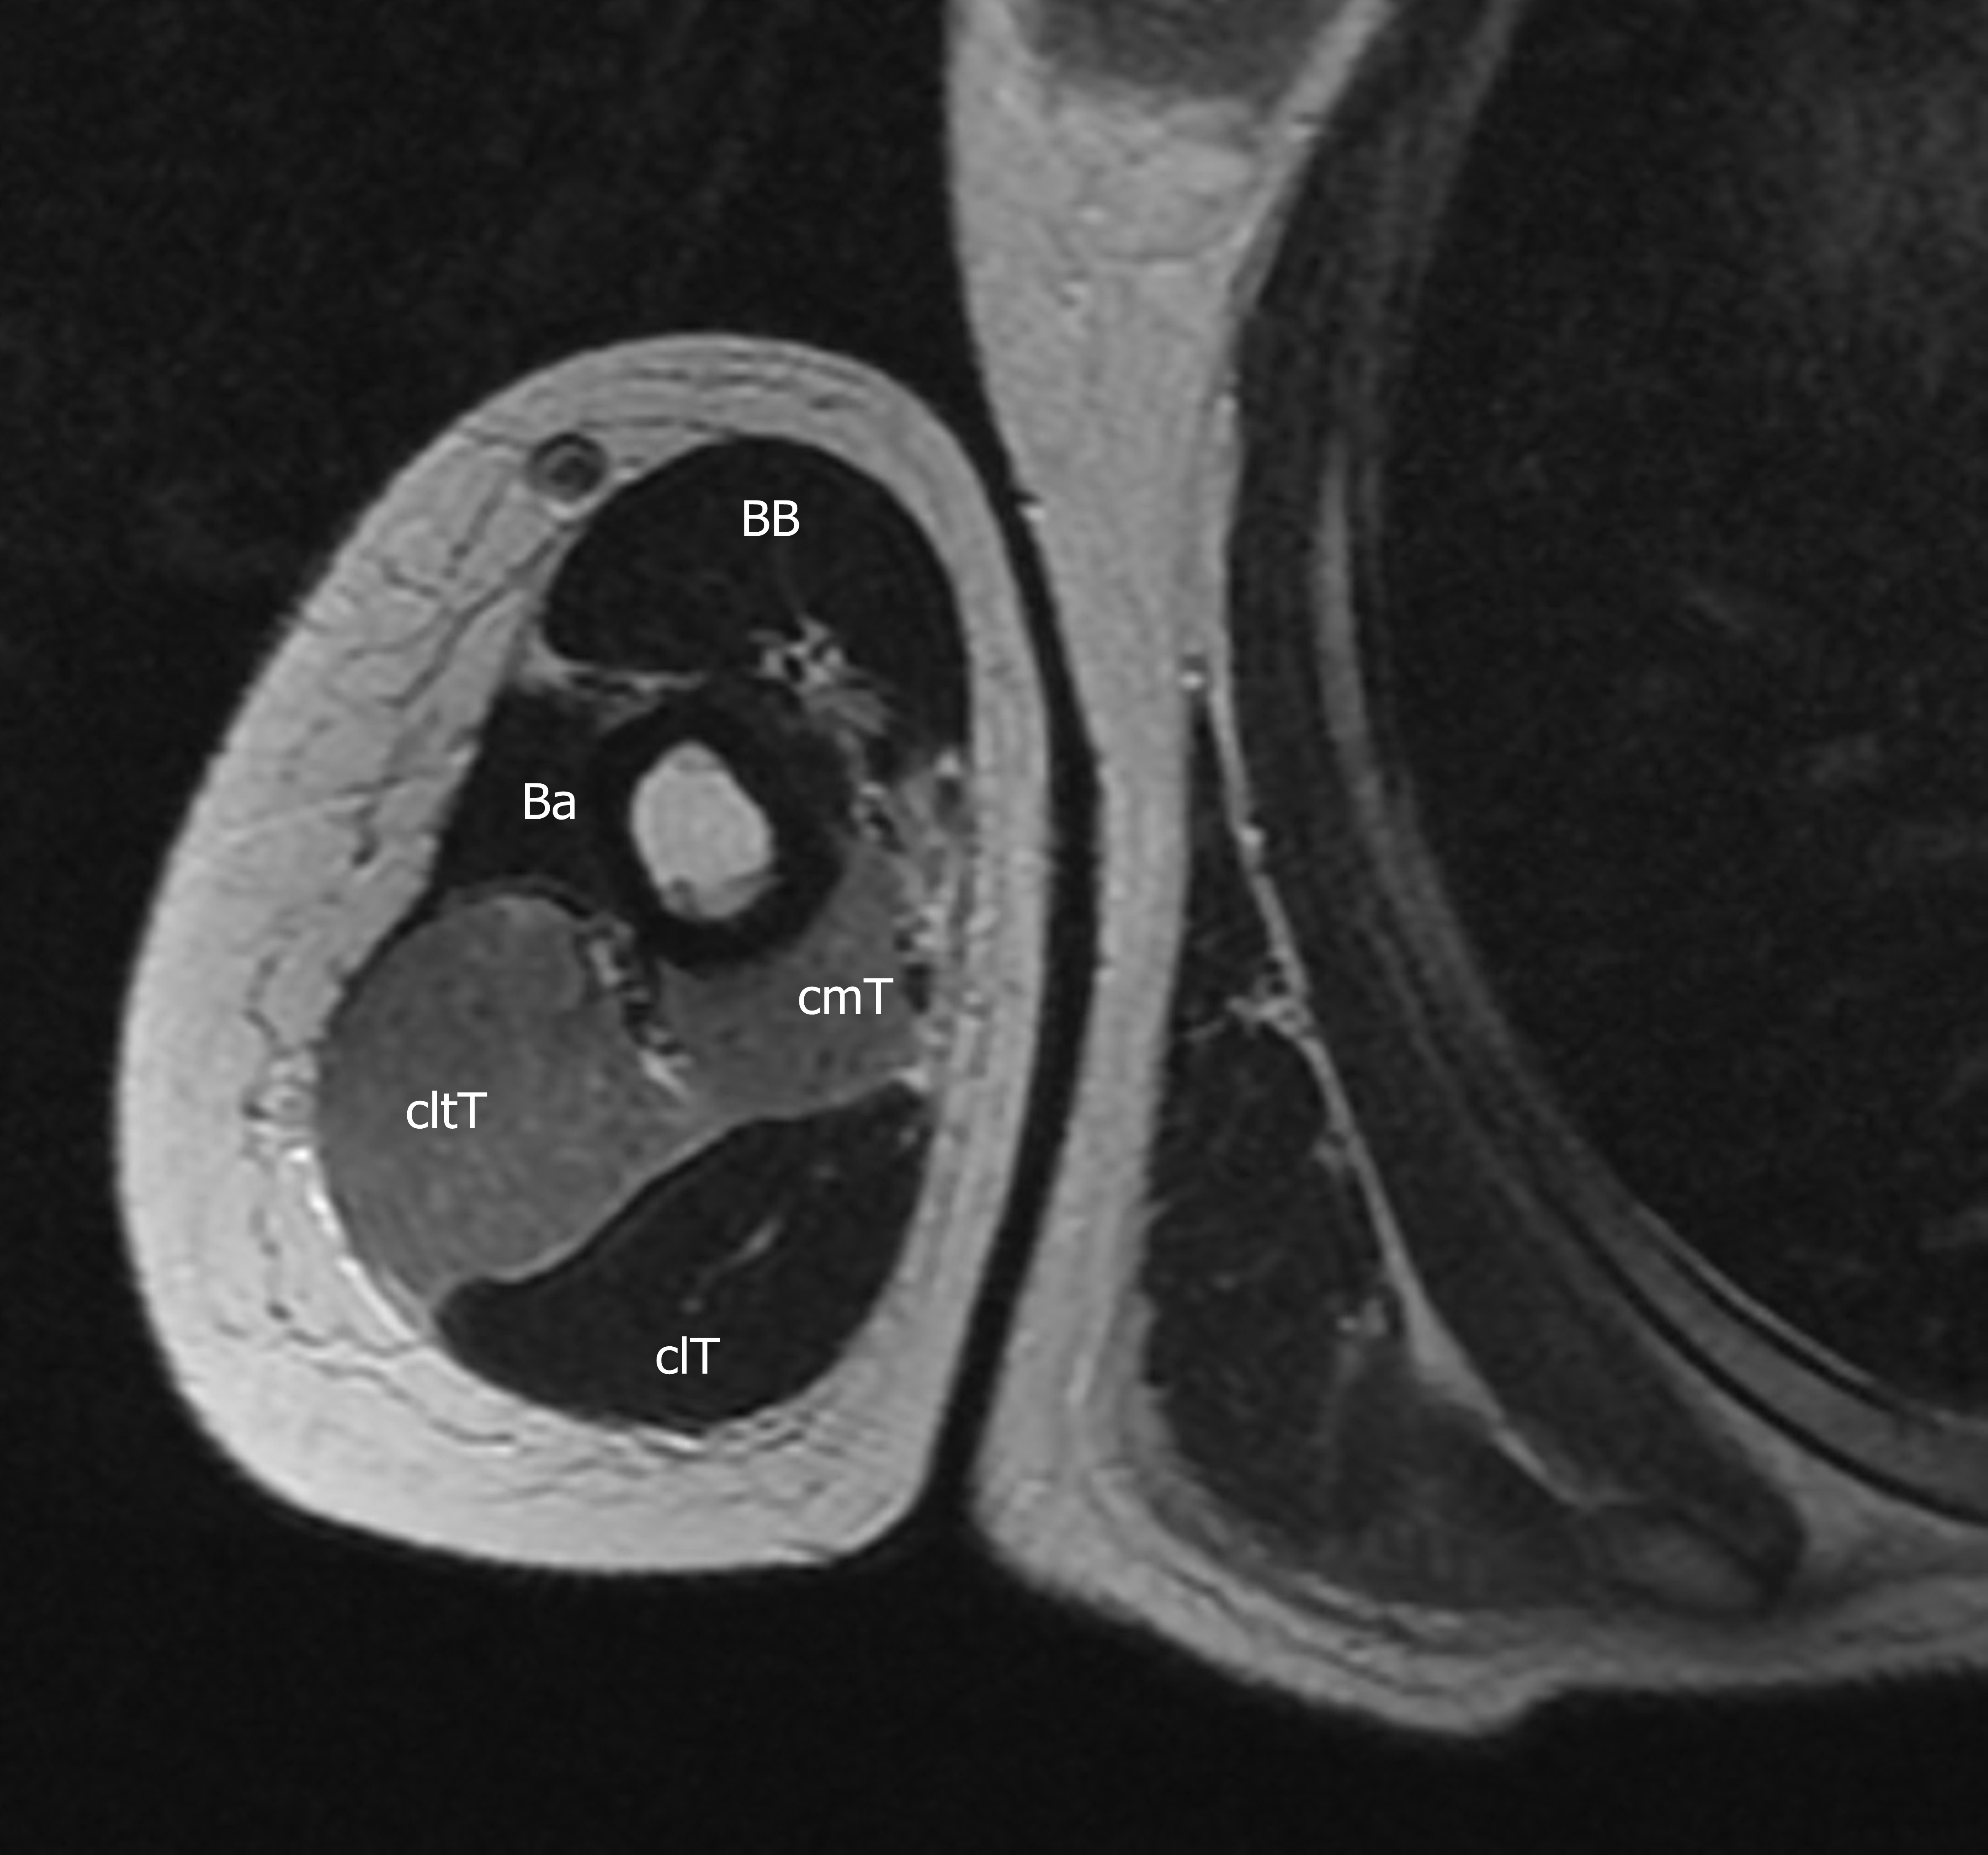

Presentación del casoMujer de 27 años de edad, con antecedentes de sepsis por estafilococo epidermidis, secundario a infección posquirúrgica de cirugía mamaria hace 3 meses, sin otros antecedentes de relevancia. Consulta en el departamento de urgencias, por presentar omalgia aguda, asociado a edema e impotencia funcional de hombro derecho, que comenzó 3 horas después de realizar actividad física intensa de CrossFit, consistente en movimientos de flexo-extensión de miembros superiores con peso.Descargas